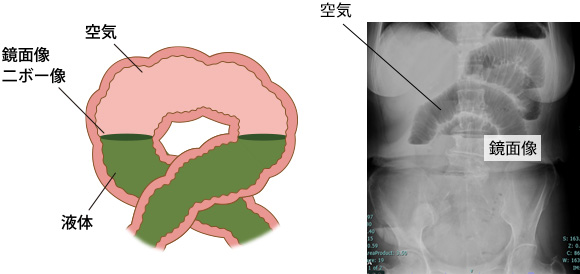

まず、医師は腹部を押して検査します。次に、聴診器を使って、発せられる音を聞きます。特に子供の場合、硬いしこりや特定の種類の音の存在は、障害が存在するかどうかを判断するのに役立つ場合があります。

その他のテストには次のようなものがあります。